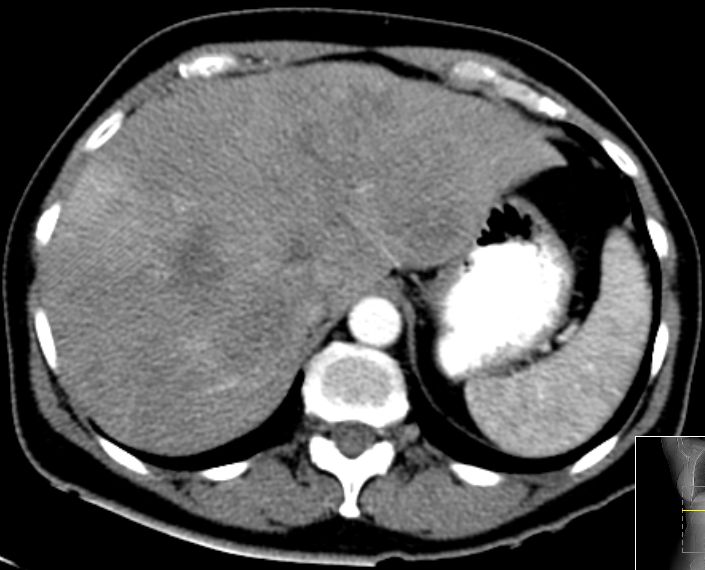

| CT | 61-jährige Frau mit Metastasenleber. Als Primärtumor wurde

ein Rektumkarzinom bei 8cm mit Lymphknotenmetastasen pararektal gefunden. Im

CT ohne KM sind keine Metastasen sichtbar.![]() |